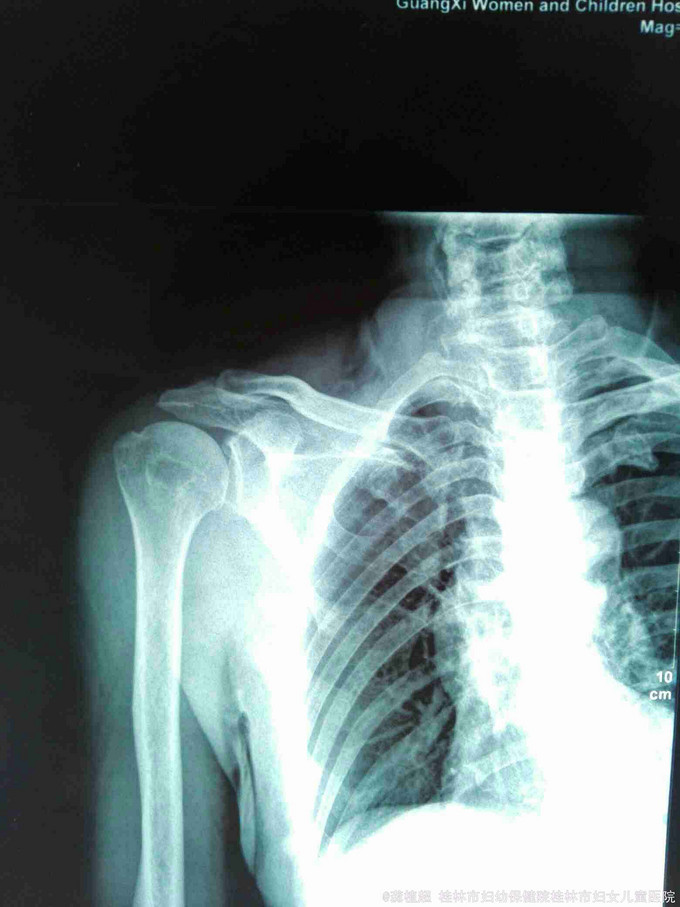

主诉:右肩外伤后疼痛、活动受限27天。 现病史:患者于2015年9月12日不慎跌倒右肩部先着地,右肩部剧烈疼痛、活动受限。肢体无麻木。在家自行外敷草药,症状无缓解。于2015年9月15日到我院门诊行X线检查提示右侧肩关节脱位。门诊予徒手复位术,疼痛明显缓解。术后复查X线示右肩关节复位良好,但患者诉右肩关节仍不能活动,同时伴有右小指麻木,第3、4指伸直受限。近3日上症加重遂来我院,行右上肢肌电图检查提示‘右侧臂丛神经损伤’,予收住院进一步诊治。饮食、睡眠、二便正常。